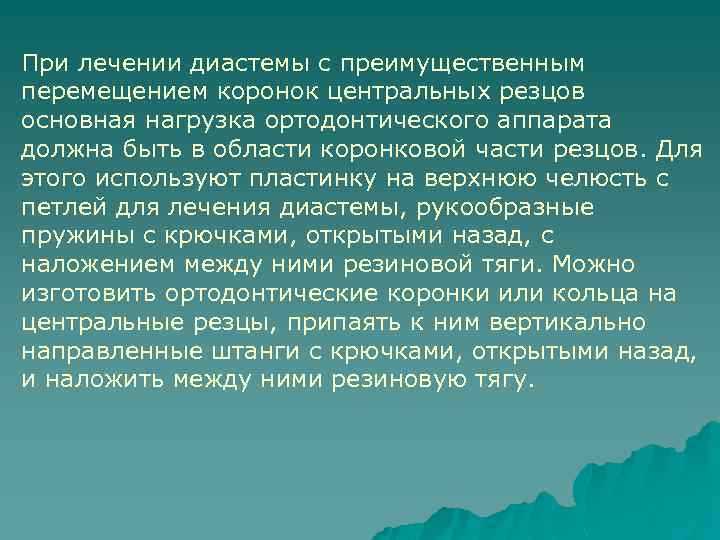

При лечении диастемы с преимущественным перемещением коронок центральных резцов основная нагрузка ортодонтического аппарата должна быть в области коронковой части резцов. Для этого используют пластинку на верхнюю челюсть с петлей для лечения диастемы, рукообразные пружины с крючками, открытыми назад, с наложением между ними резиновой тяги. Можно изготовить ортодонтические коронки или кольца на центральные резцы, припаять к ним вертикально направленные штанги с крючками, открытыми назад, и наложить между ними резиновую тягу.